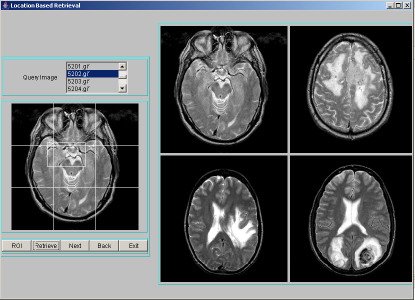

Location Based Indexing and Retrieval is performed by finding spatial location of a segmented region. The importance of location of objects is to identify the area of involvement of tumor like sensory or motor. The brain has unique areas for speech, hearing, visual, temperature regulation etc.. If the tumor which may not be centrally located, occurs at any particular area/location, then the corresponding organ gets affected. Hence location is an important feature to be indexed. To compute the location of a region, we divide the image space into 3x3 grid cells and number them 0-8 as shown in Figure 2. The region is likely to overlap number of cells in the image space. The index assigned is the cell number that is maximally covered by the region. A program segment to find location of a region is given in Table 5. We have considered an image size of 256x256 pixels in our work. The position of a region forms the location index. For each image in the database, segmentation procedure is applied to identify region-of-interest and describe segmented region by texture features: entropy, energy and contrast. Each location index stores region texture feature data along with the image object. For a query image, after finding the region-of-interest, the above mentioned texture features have to be computed and the location index is derived. Only those images that are stored at the location index matching those of the query index, are extracted as resultant target images for a given query image. These resultant images are sorted using Euclidean distance measure in the decreasing order of similarity against the query image and displayed four images at a time using JAVA-AWT based GUI. A few representative snapshots of location-based indexing and retrieval are shown in Figure 2.

|

|